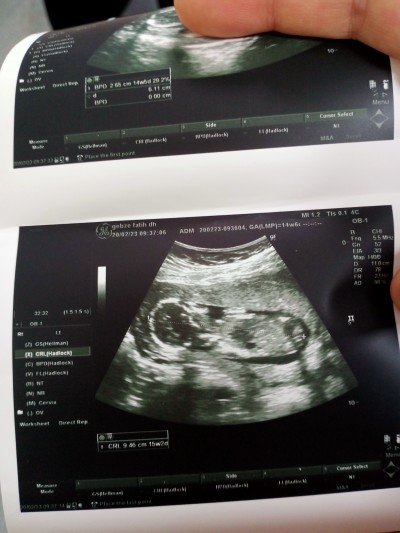

Tahmin yaparmisinz bacak arasını çok iyi saklı dedi ama başka şeylere bakarak tahmin yapabilenler vardı onlar bakabilirimi

E benim oğlum olscak ama saklıyor kendini göstermiyor doktor baya uğraştı görebilmek için

20 haftada detaylı ultrasona girecem belki diyorum kızdır ama doktor emin konuştu ☺

Kaç haftalıksin canım şuan (Hsnrmysa )

16+5 bugün. 16+0 da öğrendik ama belki kzıdır diyorum ☺

Fotoğraf hiç net değil burda tahmin değil kafadan sallama yaparlar inanmayın.